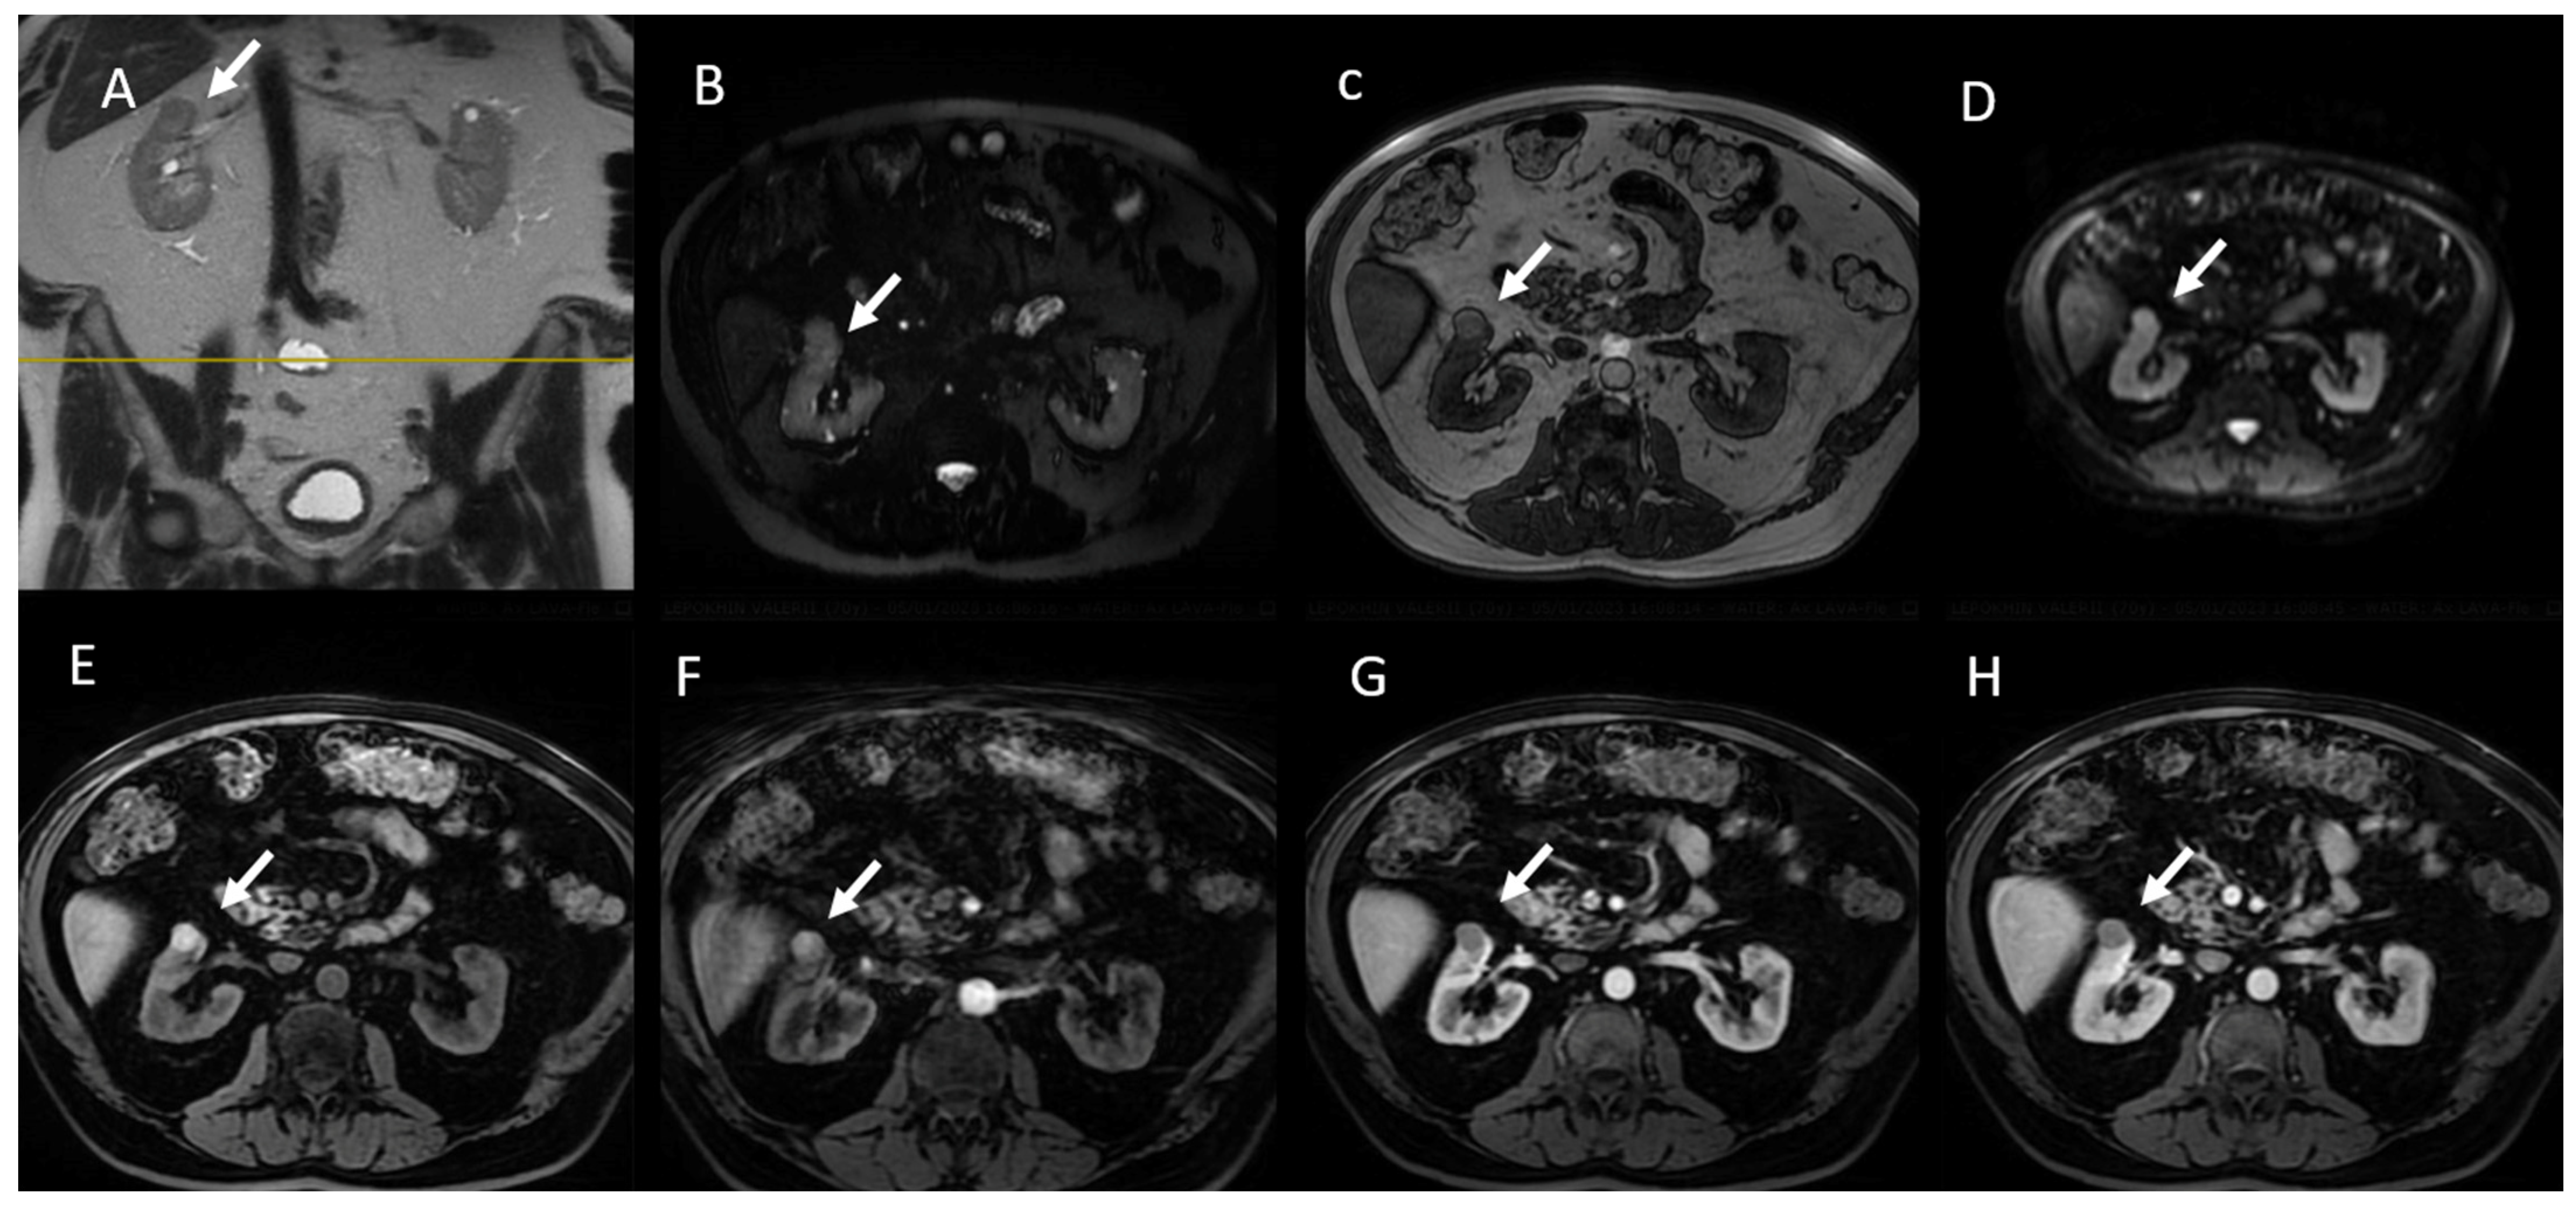

6. MRI Assessment

6.1. T2W Imaging

6.3. Diffusion-Weighted Imaging

6.4. Gadolinium-Enhanced Sequences

6.5. MRI in Bosniak Classification